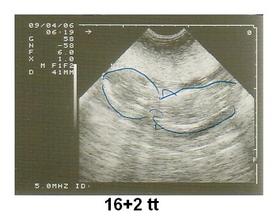

tyntyna

18. lis 2008

Honzíček

so.19.9.2009 40tt narodil se nám chlapeček Honzík v 11:25 hod. vážil 3900 g a měřil 53 cm